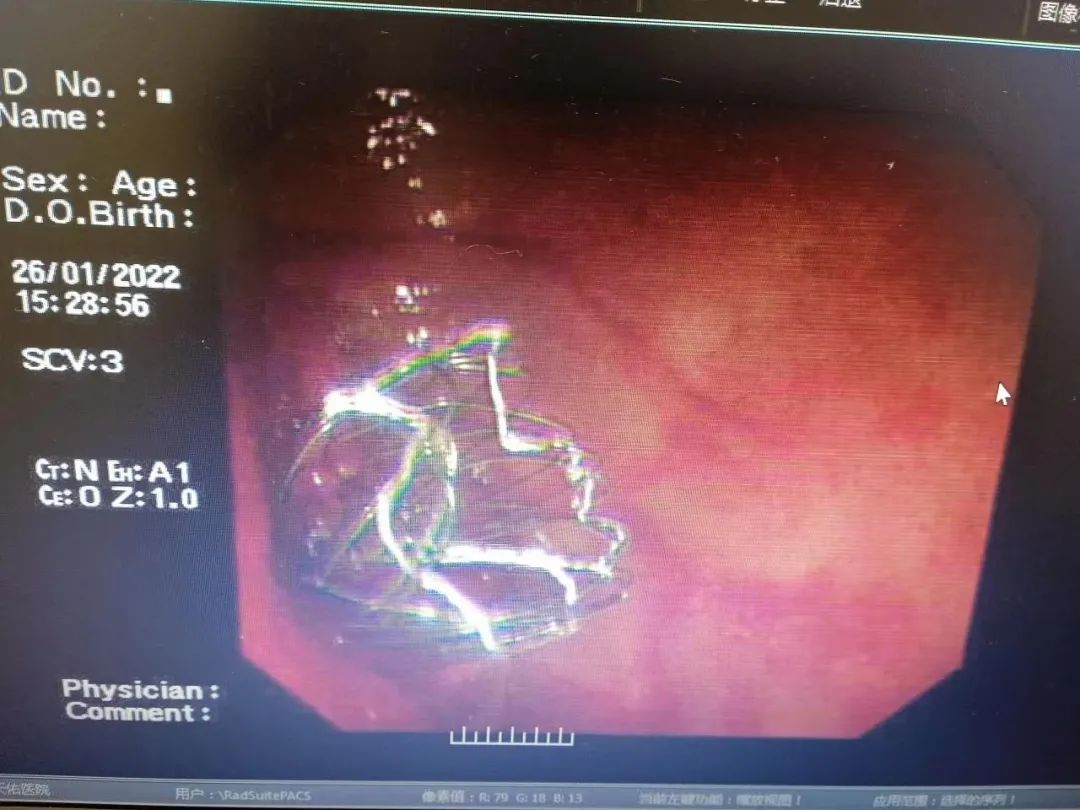

李明峰主任凭借多年来丰富的临床经验,在多次尝试的情况下终于将斑马导丝顺利通过狭窄段,在内镜的支持下最终将结肠支架置入成功,整个操作过程顺利。虽然手术经历了很长时间,但当支架置入成功的那一刻,堵在肠道内的大量粪便喷涌而出,在场的所有医务人员激动万分,完全忘记了手术过程中的艰难,也完全忽略了这股常人难以忍受的味道。

术后半小时,吴奶奶的腹胀腹痛情况明显缓解,第二天就可以进食。术后第三天复查,腹平片显示支架的位置及扩张良好。经过一段时间的调养,吴奶奶摘掉了呼吸机,各项指标逐步好转,精神状态也越来越好。

目前,吴奶奶的病情平稳。支架的成功置入,让吴奶奶的病变部位变得通畅,排便不再困难,腹痛的症状也渐渐消失。